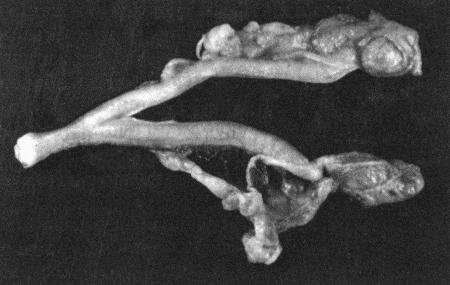

Приведенная в данной главе информация относится к сукам, неинфицированным Brucella canis. Бруцеллез может вызывать у сук бесплодие, внутриутробную гибель помета, спонтанный аборт, мертворождение и гибель щенков; у самцов в подобных случаях наблюдается эпидидимит. В Австралии и в Великобритании случаи инфицирования зарегистрированы только у импортированных животных. Тем не менее в других странах Brucella canis является одной из основных причин бесплодия. Болезни, вызываемые этим возбудителем, описаны в заключительном разделе данной главы. Бесплодие, обусловленное неспособностью к вязке или абортами, рассматривается в других главах.

Аплазия/гипоплазия яичников. Врожденное отсутствие или недоразвитие одного или обоих яичников наблюдается редко. Характерным признаком является повышение концентрации гонадотропинов в плазме в связи с недостаточностью ингибирующего воздействия гормонов яичников на гипоталамо-гипофизарную активность. В случае односторонней (но не двусторонней) аплазии стимуляционный тест с ГнРГ выявляет ответное повышение концентрации эстрадиола. Лапаротомия обнаруживает недоразвитые яичники или их отсутствие.